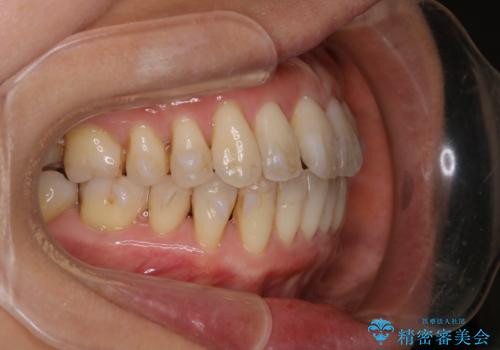

インビザラインによる非抜歯矯正を行いました。

IPRと呼ばれる、歯と歯の間を削る処置を行い、

がたつきを改善し歯を内側に入れることに成功しました。

今回のようなケースでは、

抜歯を行うことが困難であり、また歯ぐきと骨が薄いことで

拡大と呼ばれる歯のアーチを広げる処置を行うことも困難でした。

そこで、IPRによるスペースの確保をメインに行いました。

限度を守って歯を削ることで、知覚過敏が起きたり、虫歯になりやすくなるということは起きません。

また、無理に並べるよりも歯を削って並べることで骨、歯ぐきが守られ、

結果的に歯の寿命も長くなります。